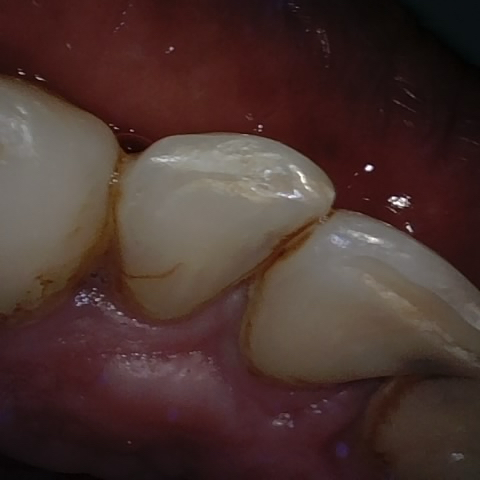

Annotated as "Good"